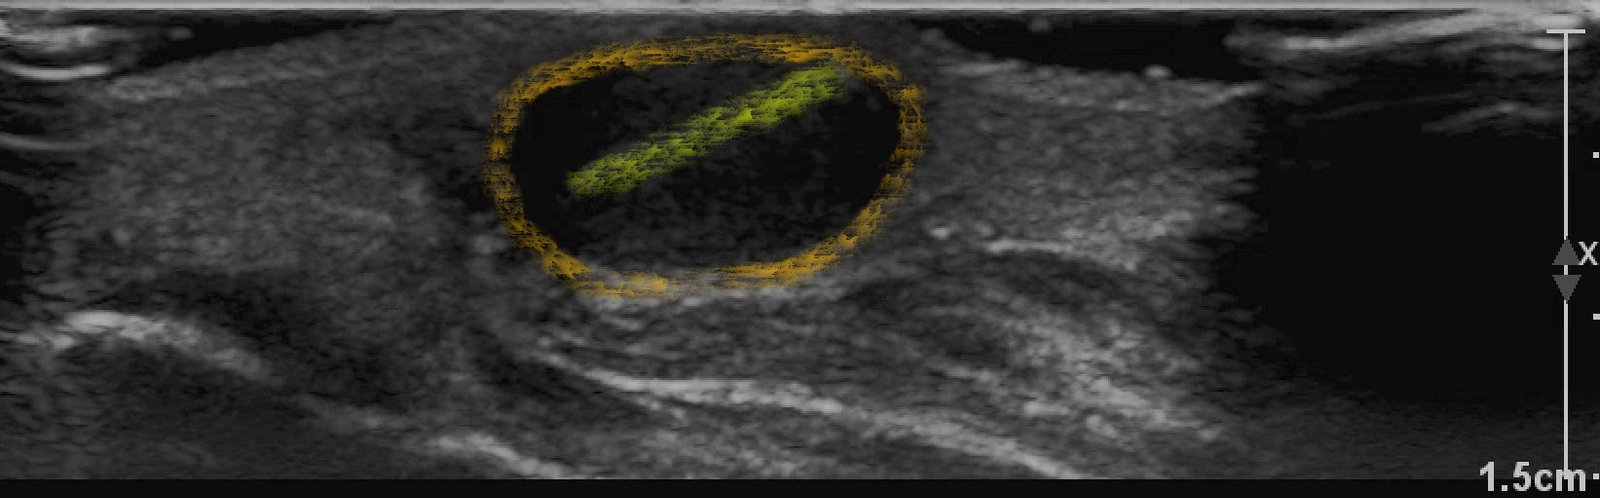

X-rays of the foot were obtained and no radiopaque foreign body was visualized. Due to high clinical suspicion for retained foreign body, a point-of-care ultrasound was performed by applying a high-frequency linear probe at the area of discomfort. In the long axis an ovoid focus of hypoechogenicity (orange outline) is visualized. Within this finding there is a linear focus (yellow line) of increased echogenicity measuring 1 mm in diameter and 1 cm in length. On short axis view, a rectangle focus (green dot) demonstrating shadowing (blue highlight) is seen.

Given the evidence of foreign body on ultrasound, incision and drainage was performed. It resulted in the removal of a 1 cm splinter along with small amount of purulent and serous fluid.